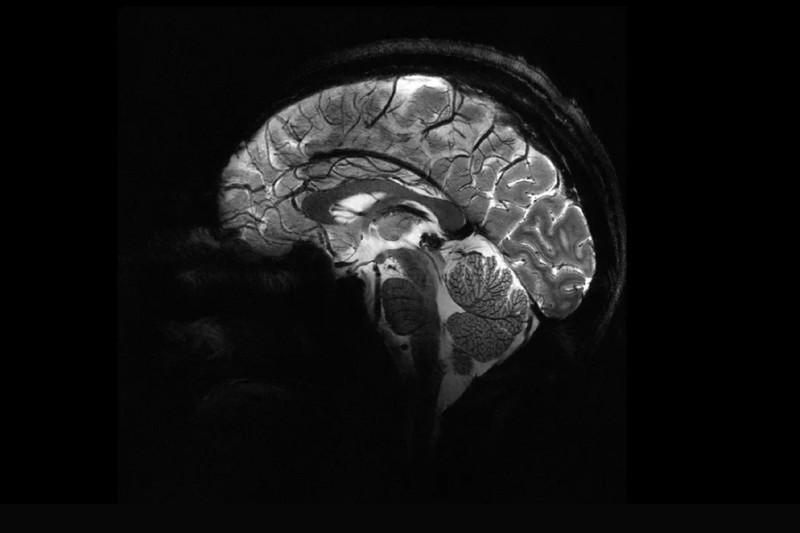

Tűpontos agyi felvétel: beüzemelték a világ legerősebb MRI gépét

A gép alig négy perc alatt olyan részletes agyképet készített, amelyet eddig több órányi munkával sem.